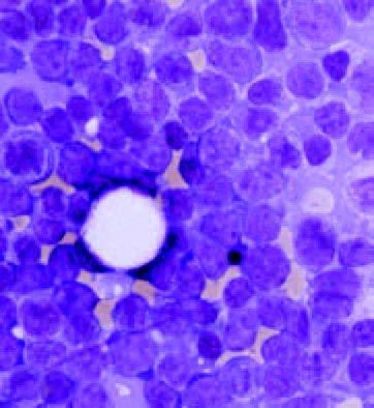

Facharztkurs am UKM: "Hämatologie und Internistische Onkologie" (10 Vortragsabende bis März 2015)

Facharztkurs am UKM: "Hämatologie und Internistische Onkologie" (10 Vortragsabende bis März 2015)

"Tag der Krebsforschung" am UKM

"Tag der Krebsforschung" am UKM